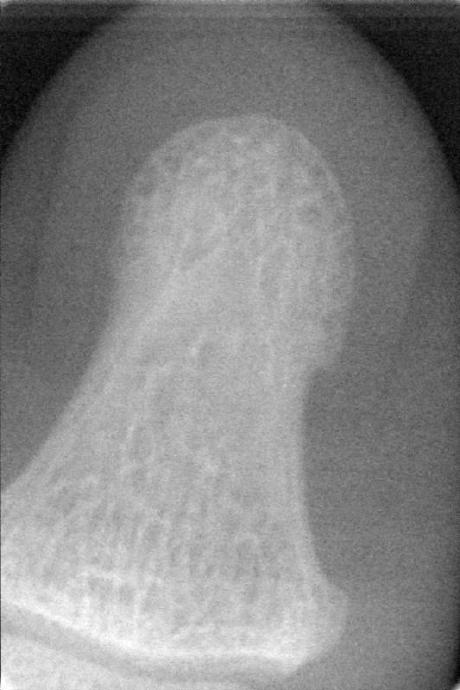

2009年,设计完成了基于英国E2V牙科口内X射线CCD的成像电路设计。设计采用了FPGA(现场可编程门阵列)及高精度ADC,通过高速USB2.0进行高速数据传输。实验结果表明:牙科口内数字成像系统分辨率15lp/mm。该X射线数字成像系统具有体积小、结构简单、分辨率高的特点,能够满足牙齿及指关节等部位实时诊断和工业X射线检测的要求。

本文介绍了一种基于英国E2V牙科口内X射线CCD的成像电路设计,该设计采用FPGA及高精度ADC,并通过USB2.0进行高速数据传输。系统具有体积小、结构简单、分辨率高等特点,适用于牙齿及指关节等部位的实时诊断。